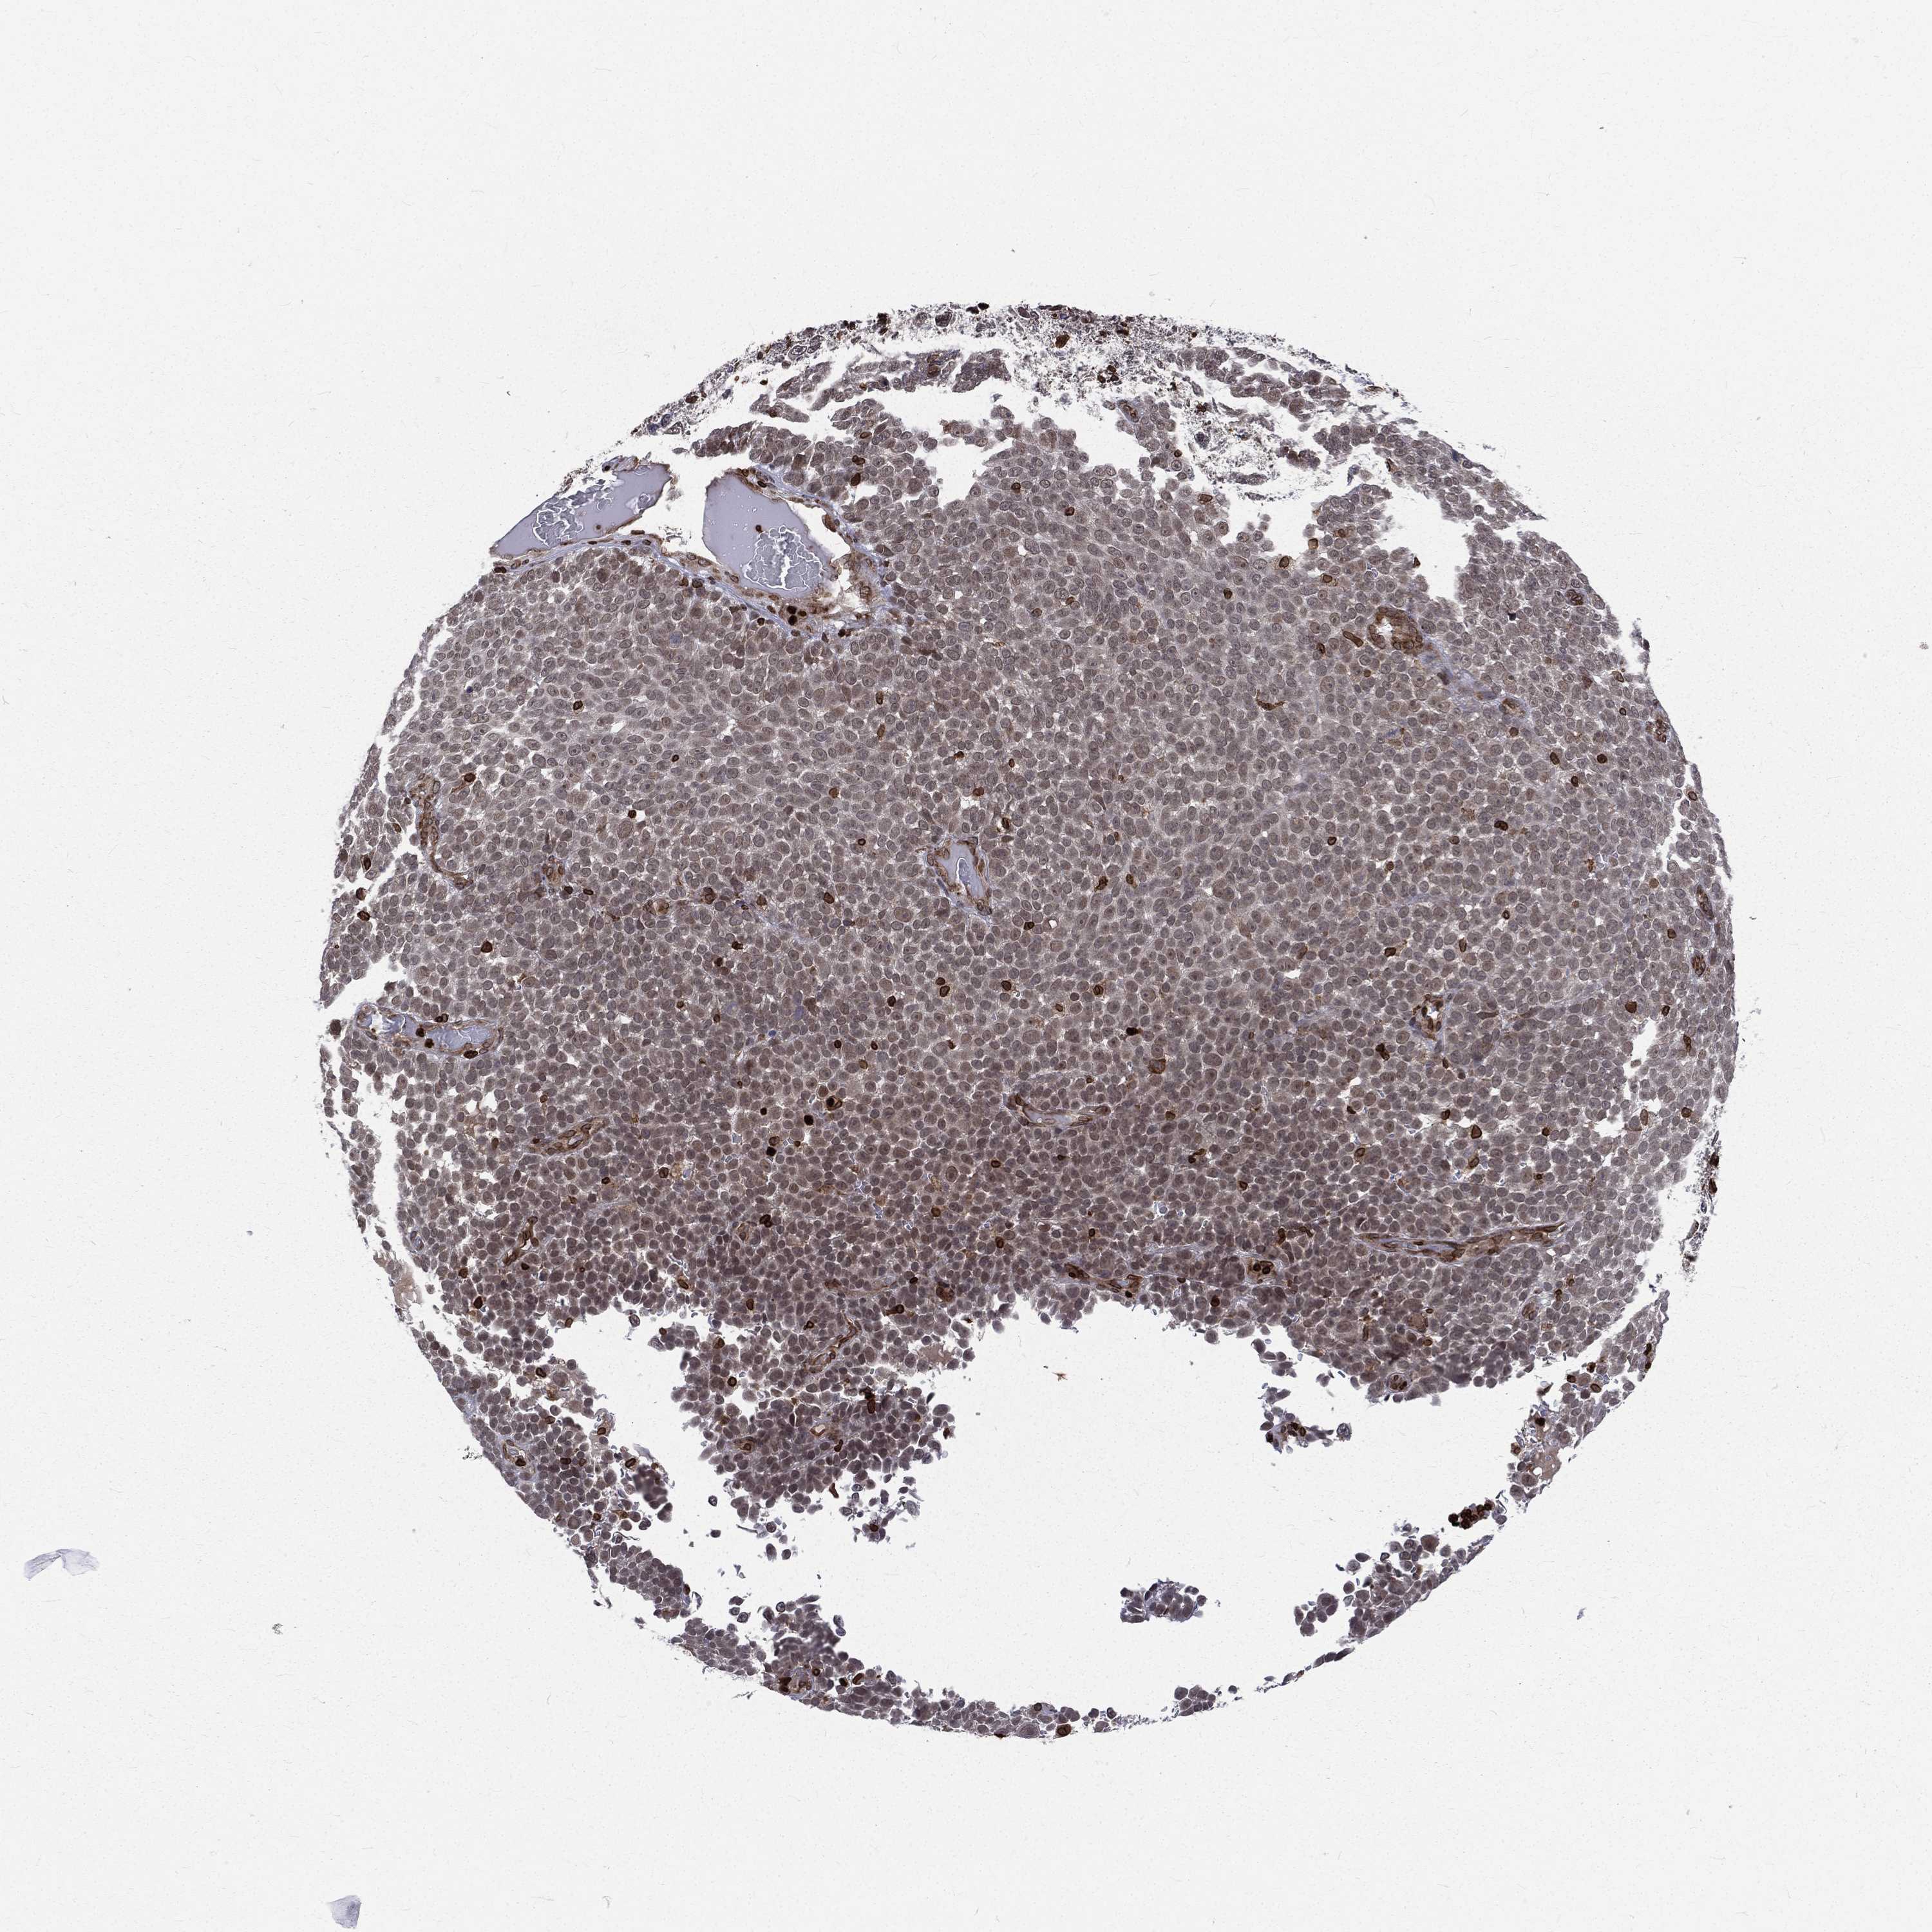

MELANOMA - Protein expressioni

A mouse-over function shows sample information and annotation data. Click on an image to view it in a full screen mode. Samples can be filtered based on level of antibody staining by selecting one or several of the following categories: high, medium, low and not detected. The assay and annotation is described here.

Note that samples used for immunohistochemistry by the Human Protein Atlas do not correspond to samples in the TCGA dataset.

Antibody stainingi

Antibody staining in the annotated cell types in the current human tissue is reported as not detected, low, medium, or high, based on conventional immunohistochemistry profiling in selected tissues. This score is based on the combination of the staining intensity and fraction of stained cells.

Each image is clickable and will lead to virtual microscopy that enables deeper exploration of all samples and also displays staining intensity scores, fraction scores and subcellular localization as well as patient and tissue information for each sample.

Antibody HPA049840

Antibody HPA062236

Staining

High

Medium

Low

Not detected

Intensity

Strong

Moderate

Weak

Negative

Quantity

>75%

75%-25%

<25%

None

Location

Nuclear

Cytoplasmic/membranous

Cytoplasmic/membranous,nuclear

Malignant melanoma, NOS

Malignant melanoma, Metastatic site